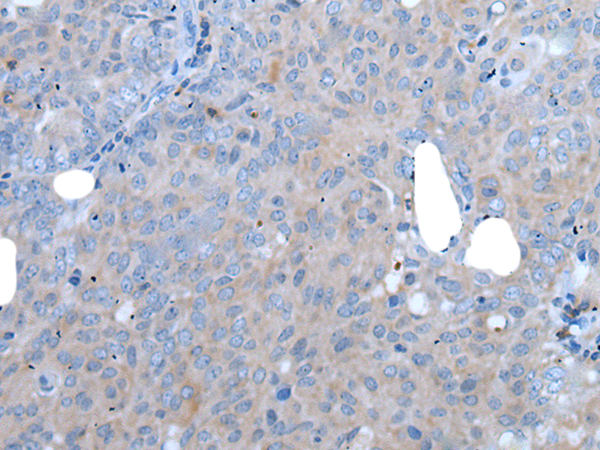

IHC positive control: |

Human cervical cancer and human tonsil |

IHC Recommend dilution: |

25-100 |